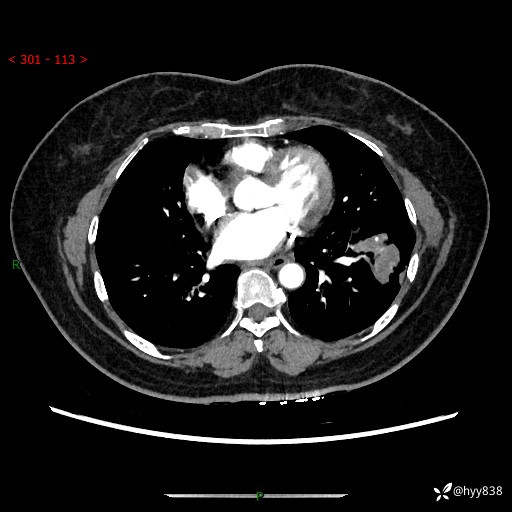

【现病史及既往史】:患者自诉2月前体检发现肺结节(左肺下叶约17mm,右肺上叶4mm),未予特殊处理,2024-10-12当地市第五医院门诊复查胸部CT提示右下肺结节(大小约3.3cm*3.9cm),患者无咳嗽、咳痰,无畏寒、发热、盗汗,无咯血,无胸闷、胸痛、呼吸困难,无恶心、呕吐,无腹痛、腹胀、腹泻等不适,现为求进一步诊治,门诊以“孤立性肺结节”收住我科。 患者本次起病来精神、食欲、睡眠尚可,大小便正常,体力、体重无明显变化。

【检查】:胸部CT增强检查